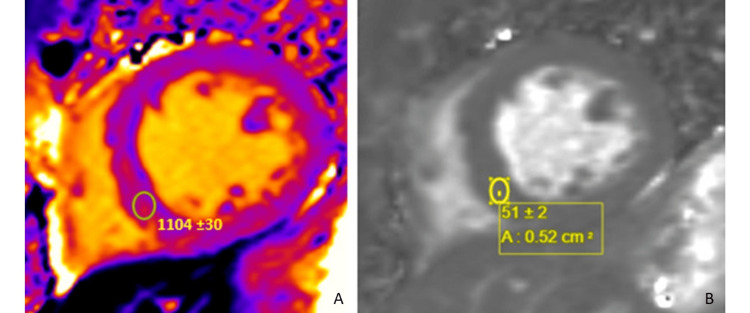

The findings were most consistent with substance abuse associated with catecholaminergic myocardial injury (mid-wall late gadolinium enhancement (LGE)) and vasospastic infarction (subendocardial late gadolinium enhancement). There was expanded interstitial volume (ECV of 47%) quantified at the septal segment, which indicated replacement fibrosis (Figure 4). There was no evidence of acute edema/inflammation based on a normal T2 mapping. He was discharged on guideline-directed medical therapy and substance abuse counseling and rehabilitation. He subsequently was admitted to a halfway house for substance abuse rehabilitation.

The CMR features of cocaine-induced myocardial injury include wall motion abnormalities, pericardial effusion, reduced myocardial perfusion, inflammation, and disease processes involving coronary arteries [ref. 3,ref. 6]. CMR sequences to assess myocardial injury include cine steady state-free precession frequency (ssfp), myocardial perfusion, T2-weighted imaging, T1-weighted imaging such as T1 mapping, and LGE [ref. 6]. Cine steady-state free precession (SSFP) MRI is a type of gradient-echo MRI pulse sequence in which a steady, residual transverse magnetization (Mxy) is maintained between successive cycles [ref. 6]. The sequence is noted for its superiority in the dynamic/cine assessment of cardiac function [ref. 6]. Myocardial perfusion imaging allows live visualization, of the lack of contrast uptake by the myocardial segments [ref. 6]. T2-weighted sequences such as triple inversion recovery and T2 mapping reflect the water composition of the myocardium and are a marker of acuity [ref. 6]. It is used to assess myocardial edema/inflammation in acute pathologies such as ischemic and nonischemic toxic myocyte damage [ref. 3]. Myocardial injury patterns with normal T2-weighted imaging suggest a nonacute process [ref. 6]. T1 mapping allows the differentiation of various tissues (fat, myocardium, and fluid) based on the tissue-specific T1 relaxation time [ref. 6]. T1 mapping can also be used to quantify the ECV fraction of the myocardium [ref. 6]. Interstitial fibrosis, considered reversible fibrosis, is the hallmark of all myopathic processes and is a major contributor to the ECV [ref. 6]. Identification of an expanded ECV gives an opportunity to halt the disease process and potentially reverse interstitial fibrosis before progression to myocyte death or replacement fibrosis [ref. 6]. LGE imaging is obtained around 10 minutes after gadolinium contrast injection. Contrast should have washed out by 10 minutes, but regions of replacement fibrosis with collagen abundance sequester contrast and remain enhanced. The pattern of LGE reflects the mechanism of injury. A subendocardial LGE indicates an ischemic injury, whereas mid-wall or subepicardial LGE indicates a nonischemic injury (myocarditis or direct myocardial injury by an offending agent) [ref. 6]. LGE can be due to an acute injury (necrosis) or remote injury (fibrosis) [ref. 6]. T2-weighted imaging for edema is interpreted in the constellation of LGE to determine the acuity of the disease [ref. 6].